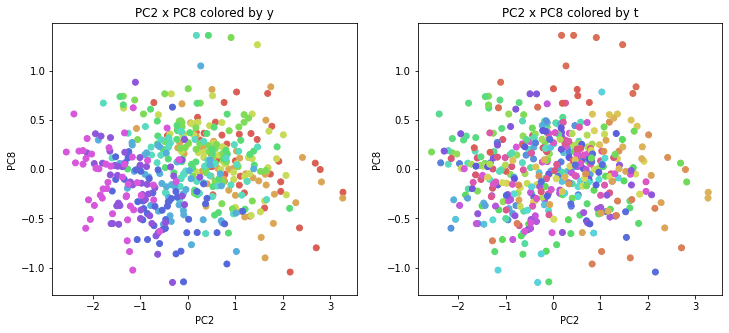

PCAの結果の第n主成分をPCnと表記します。

医療費データの場合と同様に、PCAの結果を見やすく表示するため、seabornのカラーパレットを使って、年月別、都道府県別に色分けして図示してみます(左側が年月別に色分け、右側が都道府県別に色分け)。PC1~PC8まで表示しました。

医療費データの場合ほどはっきりとはしていませんが、PC2が概ね時間の経過を表す成分で、残りの成分が時点によって変わらない地域の特徴を表す成分となっているようです。

また、PC1×PC3を見ると、47沖縄が他の都道府県からかなり離れたところに位置しており、沖縄の地域差が際立っているのが分かります。これは、以前別の記事で年齢階級のない健診データでPCAを実行した場合と似た結果となっています。

今回は、医療費データと同様に、健診データ240次元についてPCAを実行してみました。PCAの結果、医療費データの場合ほどはっきりしとはしていませんが、第2主成分が概ね時間の経過を表す成分で、時間軸に沿った全体的な動き(全国的な動き)を表しており、それ以外の成分が地域の特徴を表す成分で、この10年間あまり変わっていないことがわかりました。